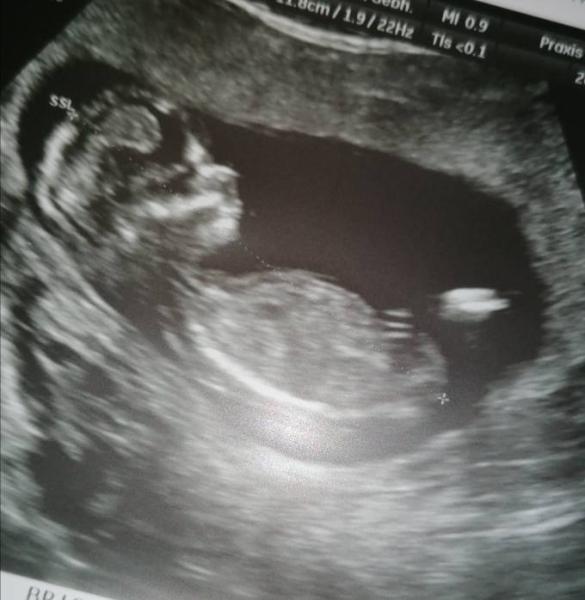

Huhu Gestern durfte ich endlich wieder zum Arzt.. Was soll ich sagen?! Ich bin jetzt schon so verliebt in den kleinen Krümel-sooo aktiv und hat kaum eine Sekunde still gehalten.. Ich bin von 12+2 auf 13+1 korrigiert worden und darf mit ET 02.06 aber weiterhin im Juni bus bleiben